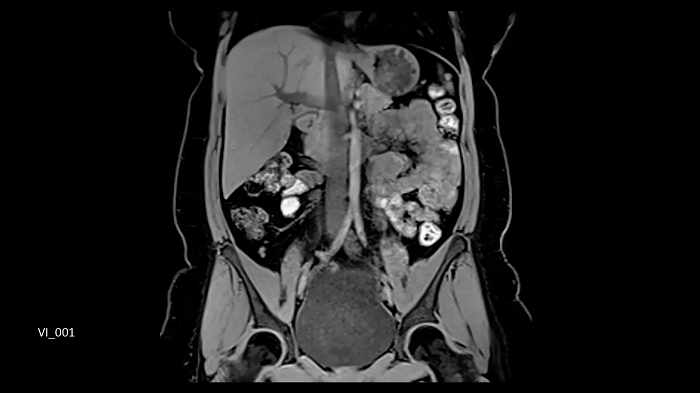

Compressed Sensing GRASP-VIBE

GRASP-VIBE Compressed Sensing for dynamic liver imaging in free-breathing patients who cannot hold their breath reliably.

- BioMatrix Spine 72

- Body 18

Image Credit: University Hospital Tübingen, Germany